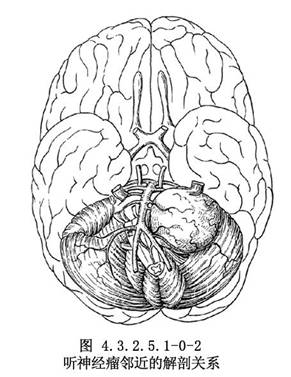

腫瘤生長過程中,向前推壓面神經與三叉神經。有時腫瘤巨大,可通過小腦幕裂孔向上生長入顱中窩。向內擠壓腦幹,超越中線。向下壓迫舌咽、迷走神經,尚可伸入枕骨大孔,個別者可長入頸內靜脈孔。內耳孔與內聽道多受破壞而擴大(圖4.3.2.5.1-0-2)。